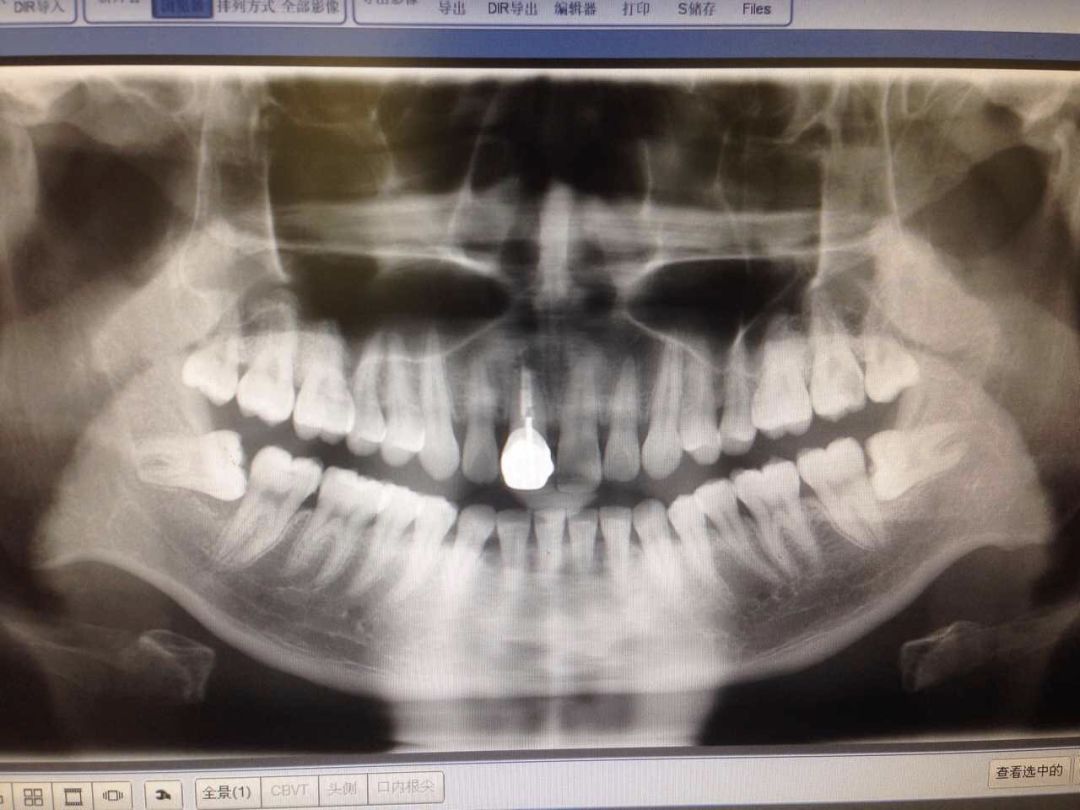

在进入正式的治疗前,需要对病牙拍一个X光片,帮忙了解牙髓的位置和牙髓形态(下图是我摔断过大门牙后处理了的X光片...)